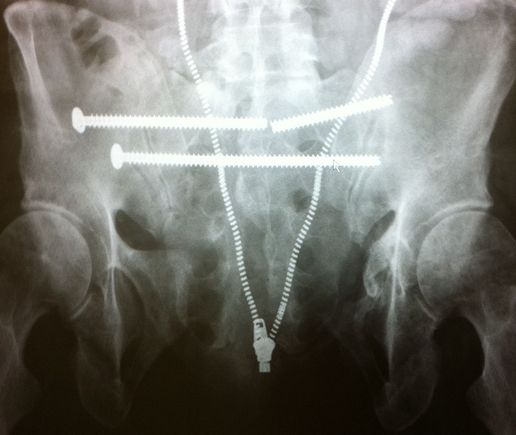

pins broke. I had t have my pelvis revised a 2nd time